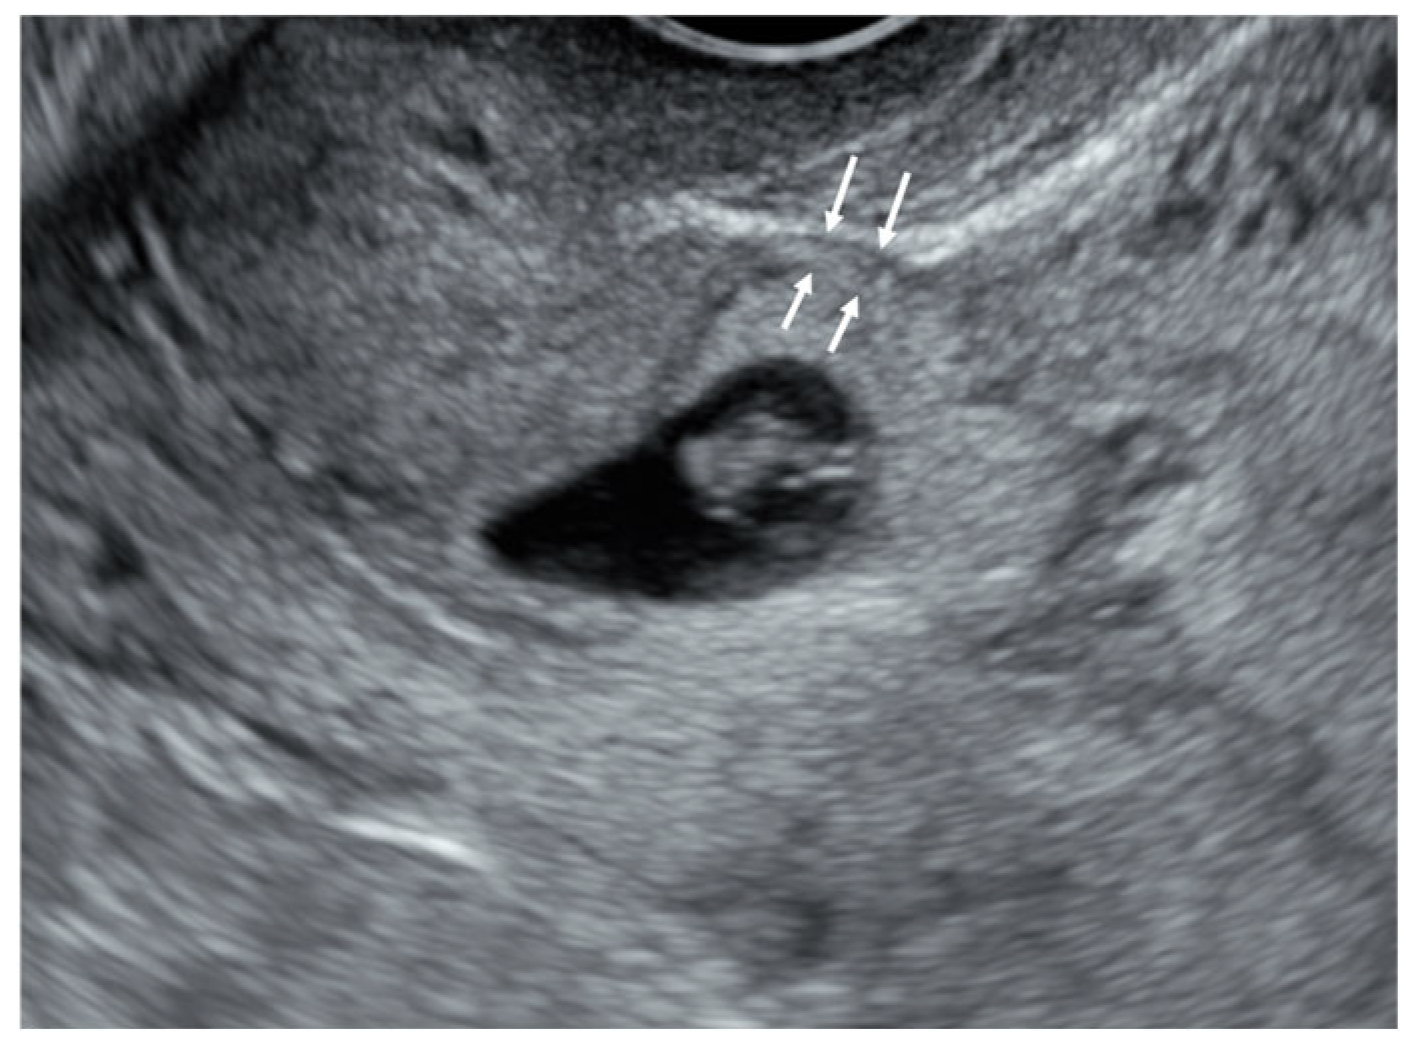

2.3. Imaging Acquisition